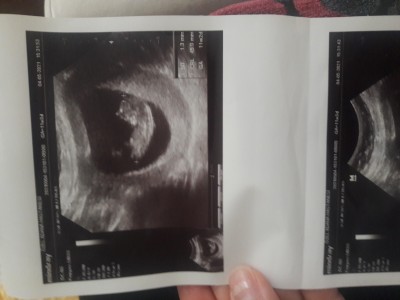

11 +2 haftalık annişler bakar mısınız

11hafta 2 günlük bebeğim

11+2

Cinsiyet tahmininde bulunursanız sevinirim

Kızların kesesi böyle yuvarlak oluyormuş sanırım doktor tahminde bulunmadı mı

Tahminde bulundu ama söylemeyin dedim yinede dayanamayıp burda sorayım dedim cinsiyet partisi yapacaz inşlh oyuzden öğrenmek istemedim